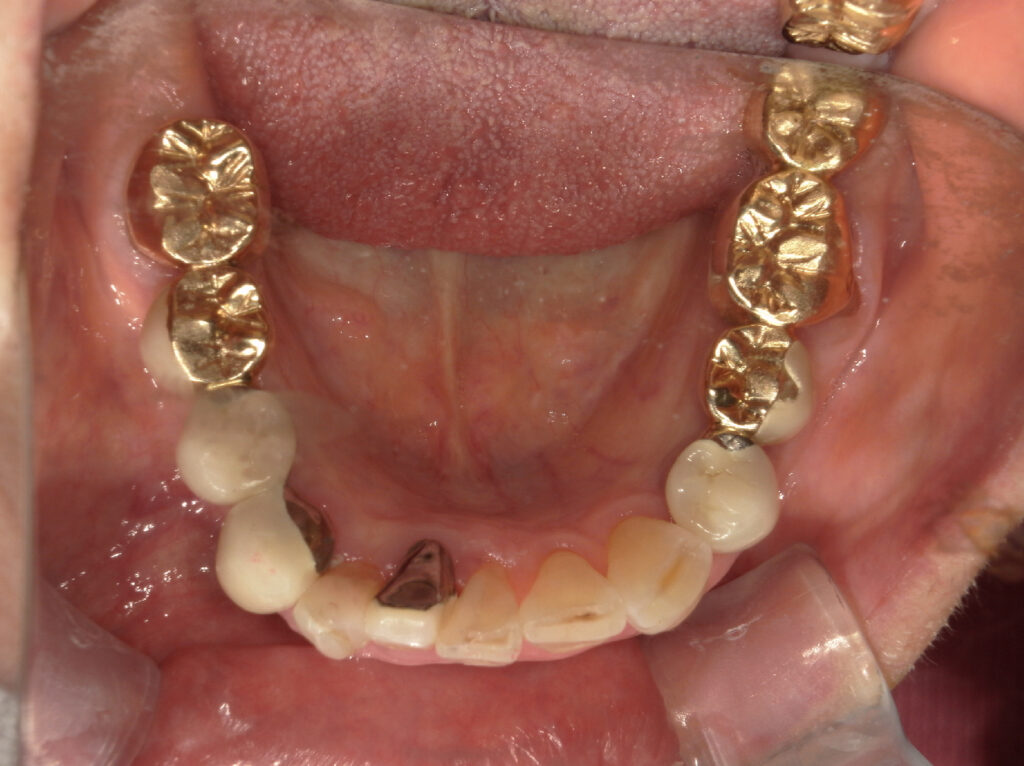

右下奥歯を2本インプラント治療した症例

| 主訴 | 右下欠けた、歯が緩む |

| 年齢 | 80代女性 |

| 治療内容 | 歯根嚢胞が大きく根管治療では限界のため抜歯しインプラント治療へ。 歯槽骨の量が不足している場合に、人工骨や自家骨を移植し、特殊な膜で覆うことで骨の再生を促し、インプラントを埋入できるようにするGBRという治療法も併用。 |

| 抜歯部位 | 右下4.6 |